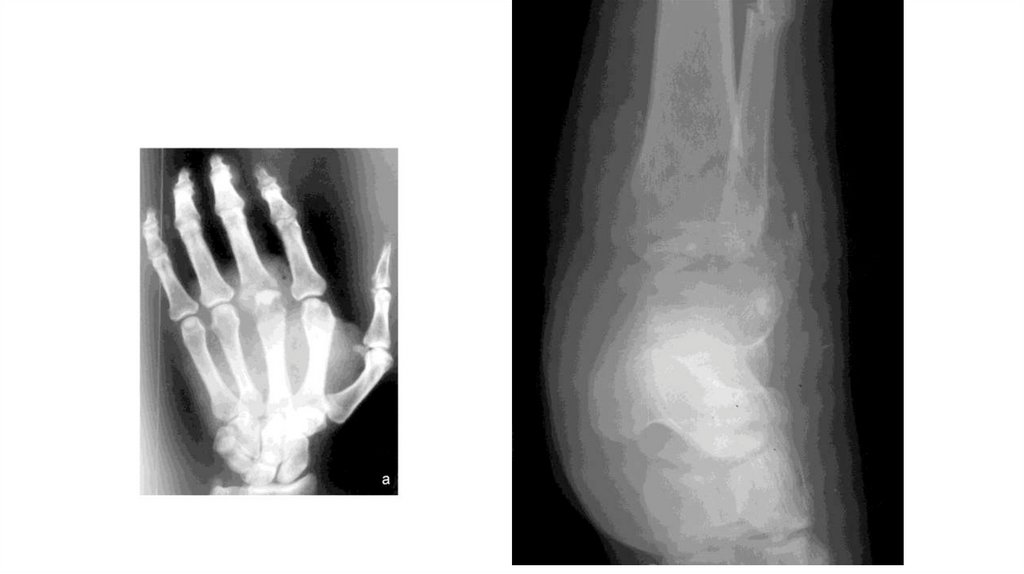

Воспалительные заболевания опорнодвигательного аппарата

«Воспалительные

заболевания опорнодвигательного аппарата»